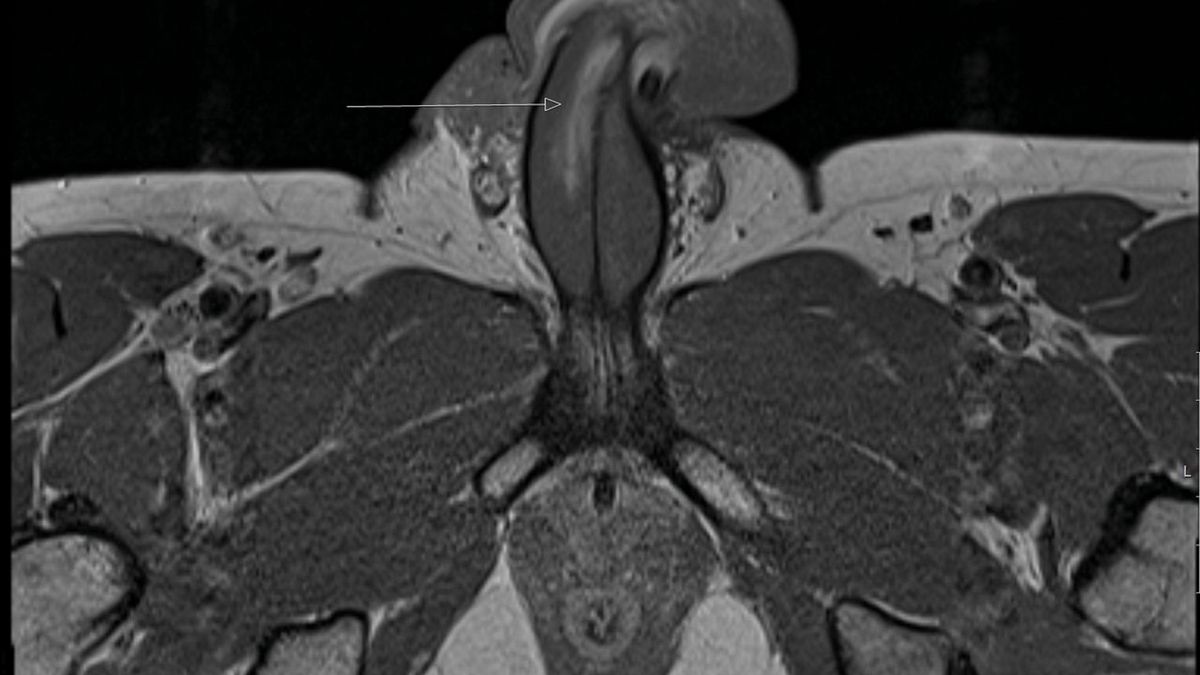

To pierwszy taki przypadek na świecie. Mężczyzna doznał pionowego złamania penisa podczas seksu ze swoją partnerką. Uraz miał aż 3 cm.

Lekarze w Wielkiej Brytanii odnotowali pierwszy znany przypadek pionowego złamania penisa podczas seksu. Członek 40-letniego mężczyzny uderzył w krocze partnerki w obszar między odbytem a genitaliami, zanim u podstawy penisa otworzyła się 3-centymetrowa "łza".

W prąciu nie ma kości, ale złamania zwykle zdarzają się, gdy penis mężczyzny wysuwa się z partnerki i nagle zostaje zgięty. Powoduje to bolesny obrzęk. Medycy, którzy leczyli pacjenta, opisali ten przypadek w "British Medical Journal". Potwierdzili wówczas również, że wszystkie wcześniej zarejestrowane złamania penisa były poziome.

Ten przypadek był jednak był inny. Rozszczepiona została albuginea tunica - warstwa ochronna wokół tkanki erekcyjnej, która pompuje krew do tego obszaru. Lekarze powiedzieli, że podczas złamania nie było słychać "trzaskania", co ma miejsce, gdy złamania są poziome.